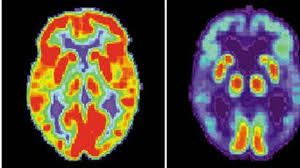

[caption id="attachment_201003" align="aligncenter" width="573"]

Photo taken from The Sun Daily[/caption]